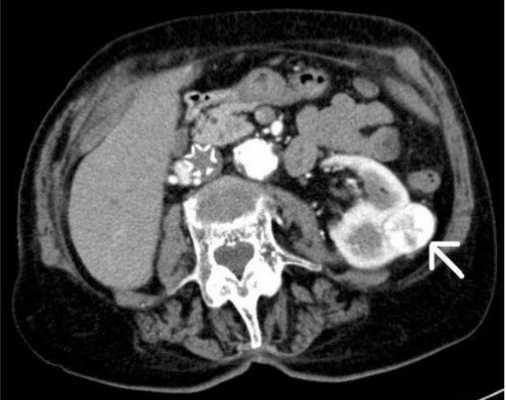

новообразованиях: оценивается их локализация, размер, вовлеченность окружающих органов и тканей. По косвенным признакам (прорастание в соседние структуры, поражение лимфоузлов) можно предполагать доброкачественный или злокачественный характер опухоли. Контрастные вещества также предоставляют больший объем о новообразованиях;

Опухоль левой почки, выявленная на КТ мочевыделительной системы с контрастом (указана стрелкой)